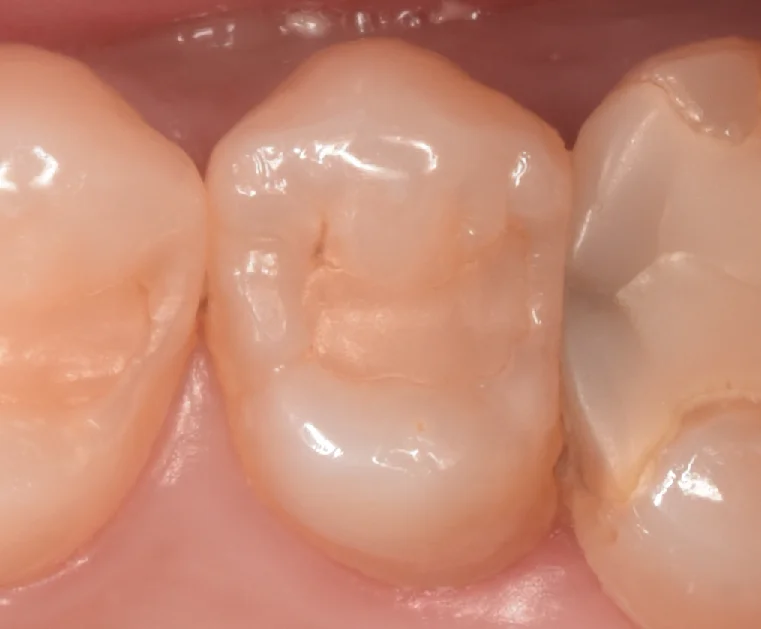

まずは術前からです。

画面中央の白い詰め物の部分が今回治療する部位になります。

隣には他院で行った自費の素材が入っています。

歯との間もきついですし、間から虫歯が入り込んでいたので、おそらくは自費の詰め物を行った際に今回治療する歯を掠ってしまい、そこから虫歯ができたのではないかと思われます。